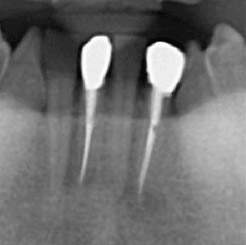

下の画像ですが、「黒い部分」が神経の入っている管であり、このすべてを綺麗に清掃する必要があります。

レントゲン

当院で処置した症例をご紹介します。

他院で抜歯と言われてしまった歯でも抜歯せずに対処した症例も多数あります。

黒い影が出ている部分が問題の個所(根尖病巣)で、治療後はこの影がなくなっているのが見て取れると思います。

• 治療前

• 治療後

保険適用。根尖病巣を治療した症例。

リスクとして、稀だが再発することがある。